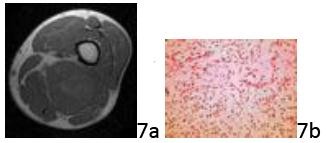

Question 7 A 36-year-old man has had an enlarging left posterior thigh soft-tissue mass for the past month, and he now reports numbness and tingling in his sciatic nerve distribution. Based on the MRI scan and biopsy specimen shown in Figures 7a and 7b, what is the most likely diagnosis?

Question 7 A 36-year-old man has had an enlarging left posterior thigh soft-tissue mass for the past month, and he now reports numbness and tingling in his sciatic nerve distribution. Based on the MRI scan and biopsy specimen shown in Figures 7a and 7b, what is the most likely diagnosis?

1. ## Myxoid liposarcoma

2. ## Synovial sarcoma

3. ## Malignant fibrous histiocytoma

4. ## Fibrosarcoma

5. ## Well-differentiated liposarcoma

DISCUSSION: Most soft-tissue sarcomas have a similar MRI appearance and cannot be differentiated by signal intensity characteristics. Histologic and often immunohistochemical analysis is necessary to subtype soft-tissue sarcomas. Myxoid liposarcomas account for one half of all liposarcomas, with a peak incidence during the fifth decade. Myxoid liposarcomas have a characteristic histologic appearance with myxoid background and an interlacing network of fine vessels. The delicate plexiform capillary vascular network is present throughout these tumors and provides an important clue for distinguishing them from myxomas. Treatment consists of wide surgical resection. Synovial sarcomas have a monophasic or biphasic histologic pattern. Malignant fibrous histiocytoma (undifferentiated pleomorphic sarcoma) is composed of pleomorphic cells in a storiform pattern. Fibrosarcoma has a typical "herringbone" pattern on low power histology. Well-differentiated liposarcoma has bland histology of adipocytes with scattered lipoblasts. The Preferred Response to Question # 7 is 1.

1. ## Myxoid liposarcoma

2. ## Synovial sarcoma

3. ## Malignant fibrous histiocytoma

4. ## Fibrosarcoma

5. ## Well-differentiated liposarcoma

DISCUSSION: Most soft-tissue sarcomas have a similar MRI appearance and cannot be differentiated by signal intensity characteristics. Histologic and often immunohistochemical analysis is necessary to subtype soft-tissue sarcomas. Myxoid liposarcomas account for one half of all liposarcomas, with a peak incidence during the fifth decade. Myxoid liposarcomas have a characteristic histologic appearance with myxoid background and an interlacing network of fine vessels. The delicate plexiform capillary vascular network is present throughout these tumors and provides an important clue for distinguishing them from myxomas. Treatment consists of wide surgical resection. Synovial sarcomas have a monophasic or biphasic histologic pattern. Malignant fibrous histiocytoma (undifferentiated pleomorphic sarcoma) is composed of pleomorphic cells in a storiform pattern. Fibrosarcoma has a typical "herringbone" pattern on low power histology. Well-differentiated liposarcoma has bland histology of adipocytes with scattered lipoblasts. The Preferred Response to Question # 7 is 1.